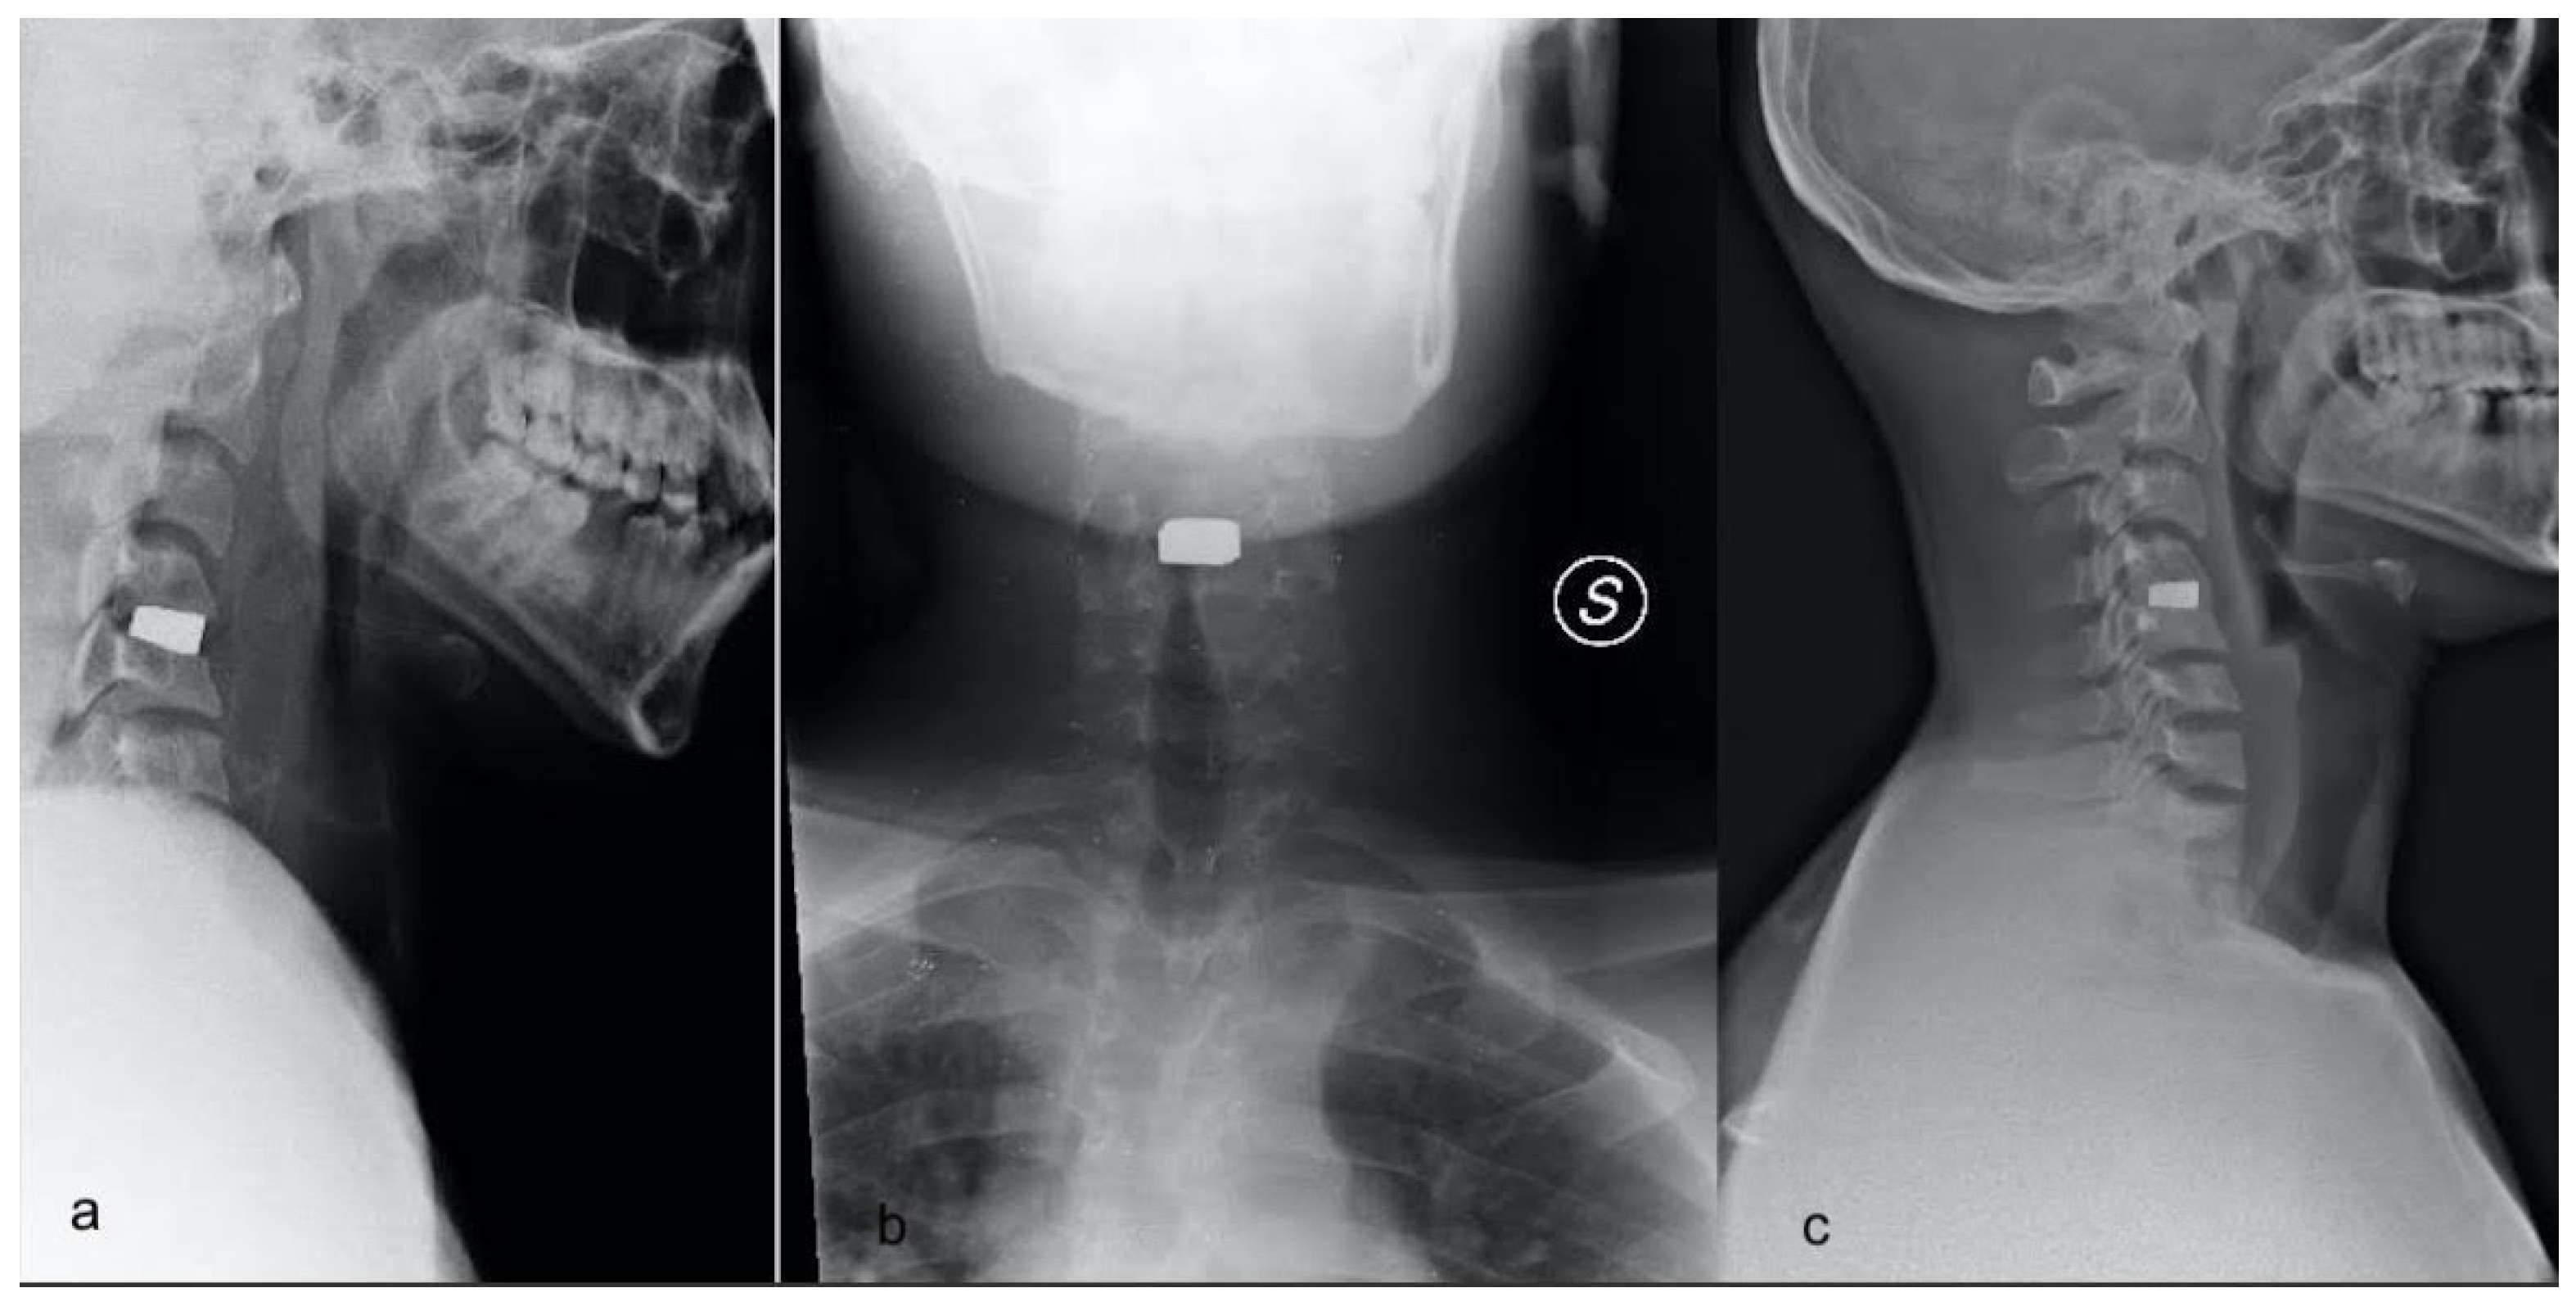

2.4. Clinical and Radiological Data